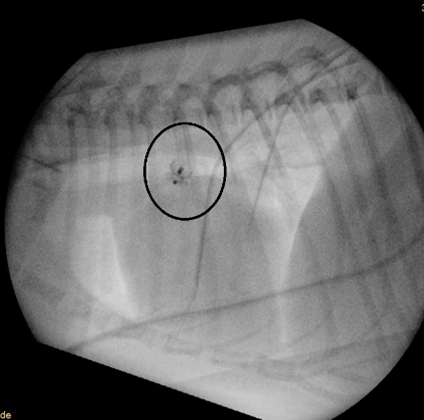

There is no proven benefit of any medical therapy for asymptomatic dogs with left-to-right PDA. If CHF is present, routine therapy should be started. Surgical closure of the PDA is considered the treatment of choice (Figure 3). This can be achieved via thoracotomy or minimally invasive techniques, such as transarterial occlusion with devices like the Amplatz Canine Duct Occluder (ACDO) (Figure 4) or Amplatzer Vascular Plug (AVP).

Surgical closure via open-heart surgery (Shimizu et al., 2006) or minimally invasive surgery using occluding devices (Bussadori et al., 2007) has been reported for dogs with moderate to large defects. Surgical closure is not recommended for right-to-left defects as this could worsen the PHT and clinical signs.